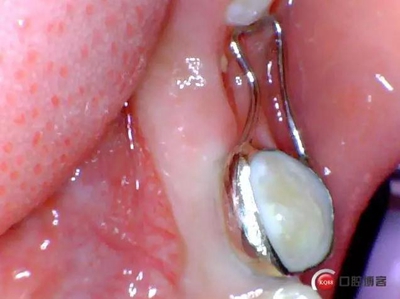

保持器回來后電話預(yù)約患者復(fù)診,反復(fù)試戴合適后消毒隔濕干燥,常規(guī)富士Ⅸ粘結(jié)保持器,調(diào)合,拋光,囑患者注意口腔衛(wèi)生并預(yù)約半年復(fù)查一次。